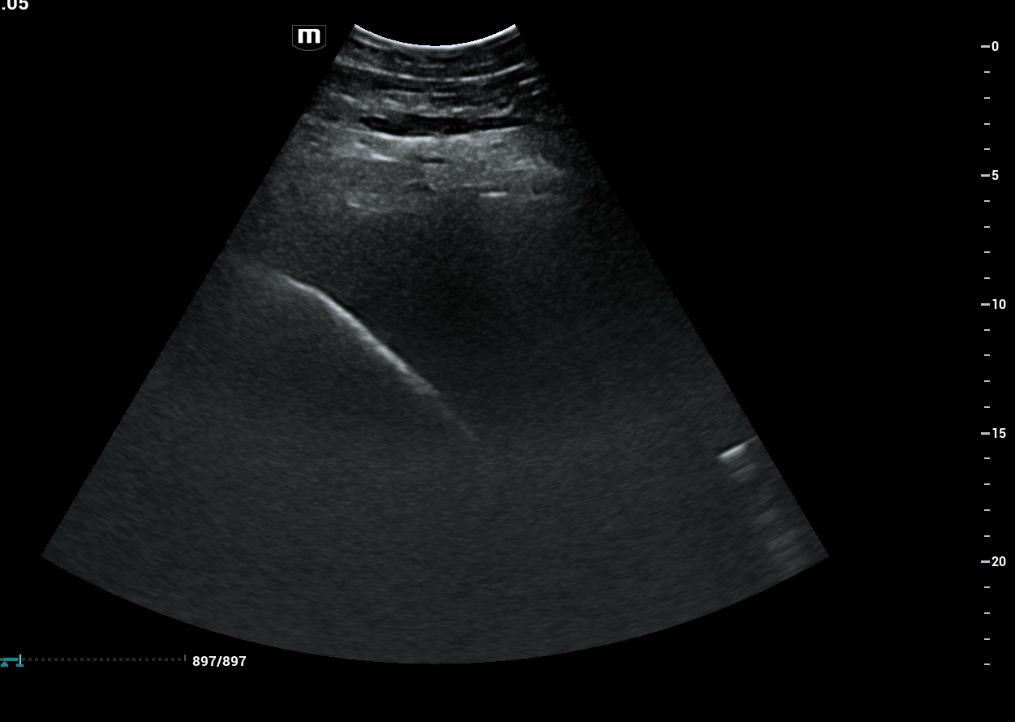

- Ultraschalluntersuchung der Leber aufgrund auffällig hoher Leberwerte im Blut

- möglicher Zusammenhang mit EMS/Übergewicht -> auch andere Ursachen bspw. Fettleber, Parasiten, Vergiftung denkbar

- Ultraschall lässt Verfettung der Leber vermuten